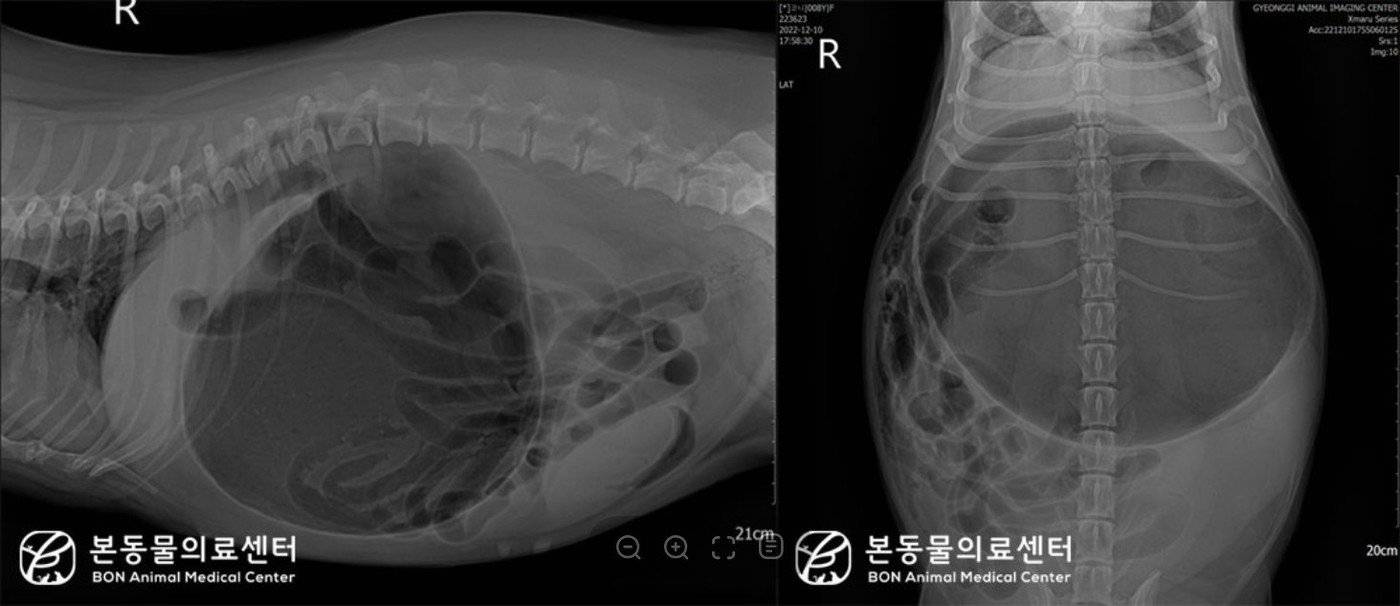

본문 이미지 - 웰시코기 반려견의 복부 방사선 사진을 찍은 결과 위의 심한 확장과 위 유문부의 등쪽, 앞쪽 변위에 따른 분획화 소견이 확인됐다. (본동물의료센터 제공) ⓒ 뉴스1

웰시코기 반려견의 복부 방사선 사진을 찍은 결과 위의 심한 확장과 위 유문부의 등쪽, 앞쪽 변위에 따른 분획화 소견이 확인됐다. (본동물의료센터 제공) ⓒ 뉴스1